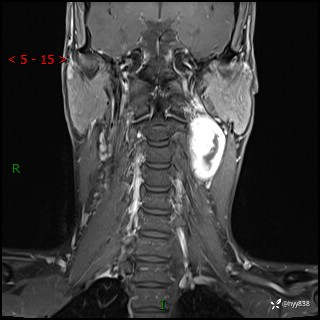

现病史:患者约3年前因感冒发现左侧颈部长一肿物,约半个鸡蛋大小,无明显疼痛及其他不适,一直未行特殊处理。3个月前发现左侧颈部肿物变大,随后至当地市第二人民医院耳鼻喉科行左侧颈部彩超示:左侧颈部囊实混合性包块;喉部MPR示:左侧胸锁乳突肌内前方占位,累及左侧喉旁间隙,建议增强扫描。建议手术治疗。患者考虑。随后至我院肿瘤科就诊,行细胞学穿刺示:考虑血管源性肿瘤可能,建议进一步检查。建议至我院口腔科就诊,行颌面部MRI示:左侧颌下腺后方团状异常信号灶,建议增强。建议手术治疗。为求进一步治疗,门诊以“左侧颈部肿物”收入院。 起病以来,患者神志清、精神良好,饮食睡眠良好,大小便正常,体重未见明显变化。

颈部MRI平扫+增强